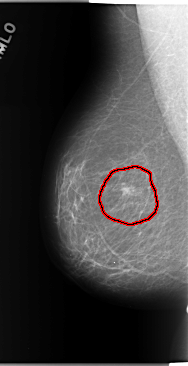

C_0143_1.RIGHT_CC

FILE: C_0143_1.RIGHT_CC.OVERLAY

TOTAL_ABNORMALITIES 1

ABNORMALITY 1

LESION_TYPE MASS SHAPE ROUND MARGINS SPICULATED

ASSESSMENT 5

SUBTLETY 5

PATHOLOGY MALIGNANT

TOTAL_OUTLINES 1

BOUNDARY